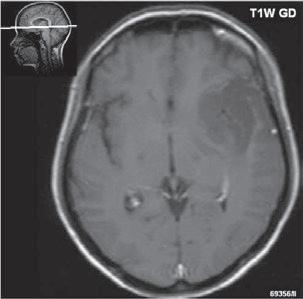

Roztroušená skleróza (RS) 189

Neuromyelitis optica (NMO) – Devicova nemoc 196

Akutní diseminovaná encefalomyelitida (ADEM) 199

Progresivní multifokální leukoencefalopatie (PML)